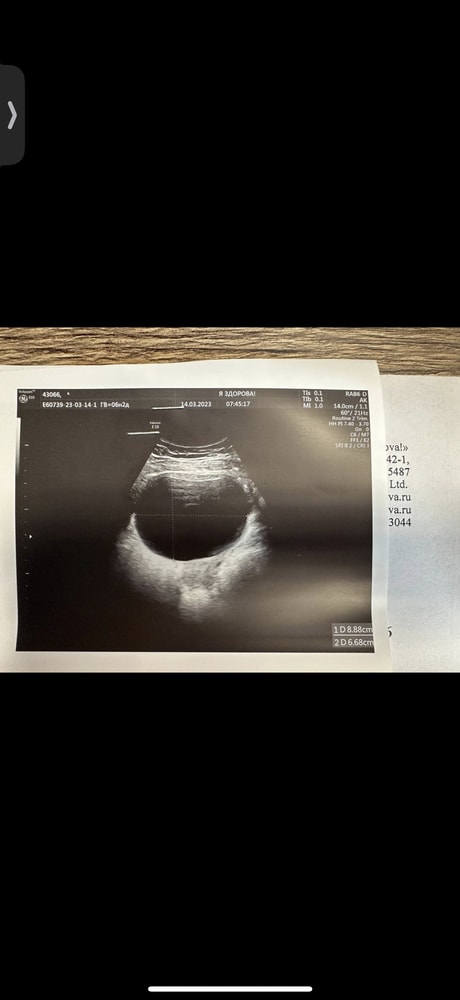

Н, слушай!!)) у меня в первую беременность была ОГРОМНАЯ КИСТА жт, 10см максимальный размер. С 12ой недели начала сдуваться, к 16 недели сдулась совсем. Моя врач мне строго настрого запретила активный спорт и секс. Эта киста должна сдуваться, но бывают истории, когда она не сдувается. И вот в таком случае делают лапароскопию беременной женщине. Как раз таки у моего врача был такой опыт с дочкой) я была так напугана, а она меня успокоила. Сказала, что в ее случае киста жт не сдулась и ей делали операцию на 16 неделе. Все прошло супер, дочке уже 14 лет) Поэтому не переживай и не волнуйся!) скорее всего киста исчезнет к концу первого триместра

Н, вот моя киста в первую беременность Изображение